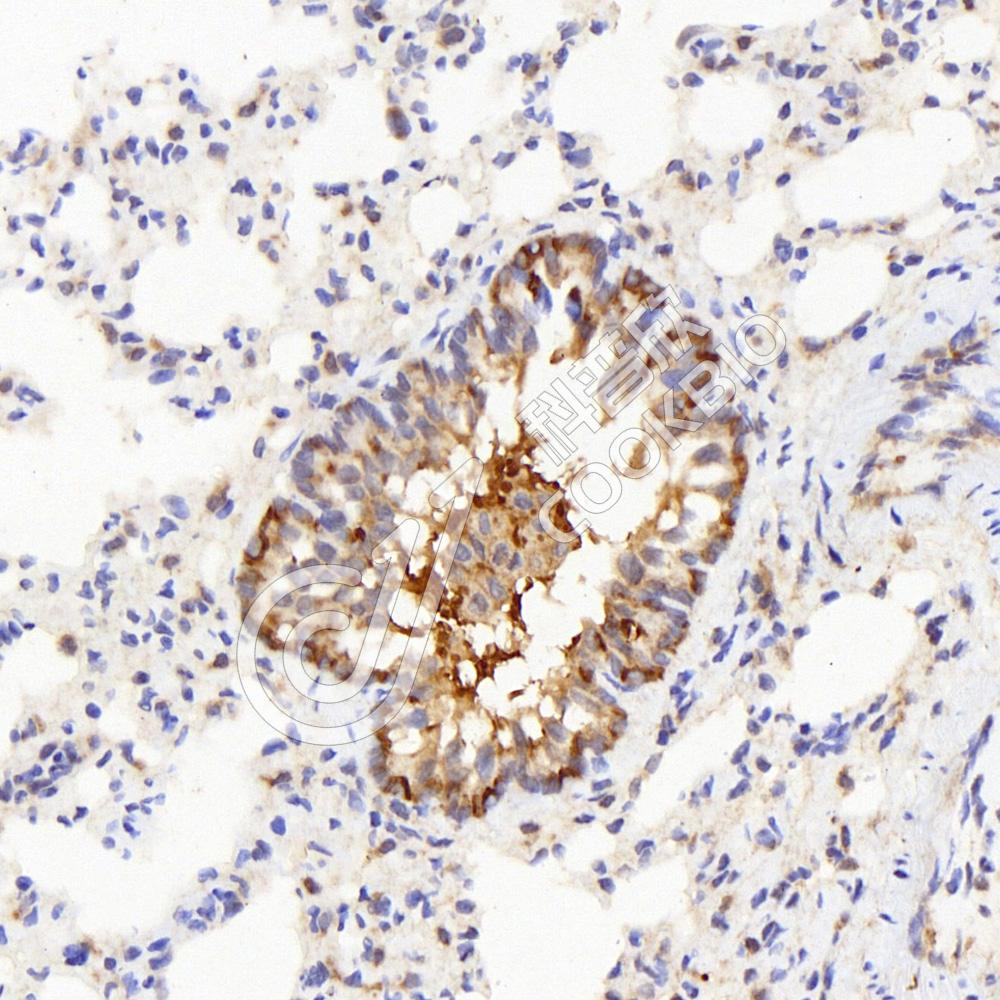

IF检测IL-2 Receptor alpha蛋白(货号 K134836)(红色).

样品: 大鼠脾, 4%多聚甲醛 (货号KSG1101) 固定12-24小时.

抗原修复: Tris-EDTA抗原修复液(pH 9.0) (KSG1203), 98℃, 20分钟.

封闭: 3% BSA(货号KSGC305010)的PBS溶液, 室温孵育30分钟.

—抗: 1: 600稀释, 4℃ 孵育过夜.

二抗: Cy3标记山羊抗兔IgG (H+L) (货号KB63909), 1: 300稀释, 室温孵育1小时.